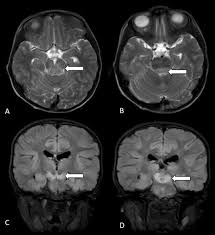

panda sign

symmetric hyperintensities of putamen > caudate, thalamus, brainstem; red nuclei are eyes

wilson’s disease

from copper deposition